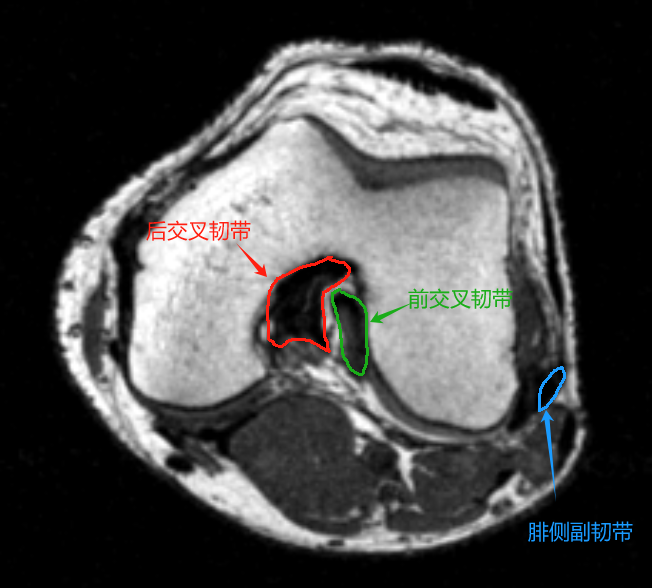

1. 韧带与肌腱

• 前交叉韧带(ACL):外侧髁间嵴至股骨外侧髁内侧面,轴位呈束状低信号。

• 后交叉韧带(PCL):胫骨后方至股骨内侧髁,轴位为卵圆形低信号结构。

• 内侧副韧带(MCL):分浅深两层,浅层为条带状低信号,深层与关节囊融合。

• 外侧副韧带(LCL):条索状低信号,连接股骨外上髁与腓骨头。